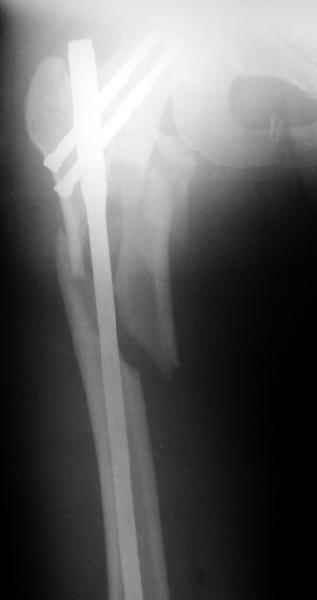

Другое наблюдение:Мужчина, 1957 г.р. Травма в результате ДТП 12.09.04г.

Диагноз: Закрытый оскольчатый подвертельный перелом правой бедренной кости со смещением отломков, оскольчатый перелом большого вертела, отрывной перелом малого вертела.Сопутствующие заболевания: Язвенная болезнь желудка, ремиссия.

Наверно, можно и так сказать, но можно и тоже самое - 4-фрагментный вертельный перелом. Выбор тот же, но с учетом молодого возраста реконструкционный гвоздь тут более применим. Вот уже наш пример.